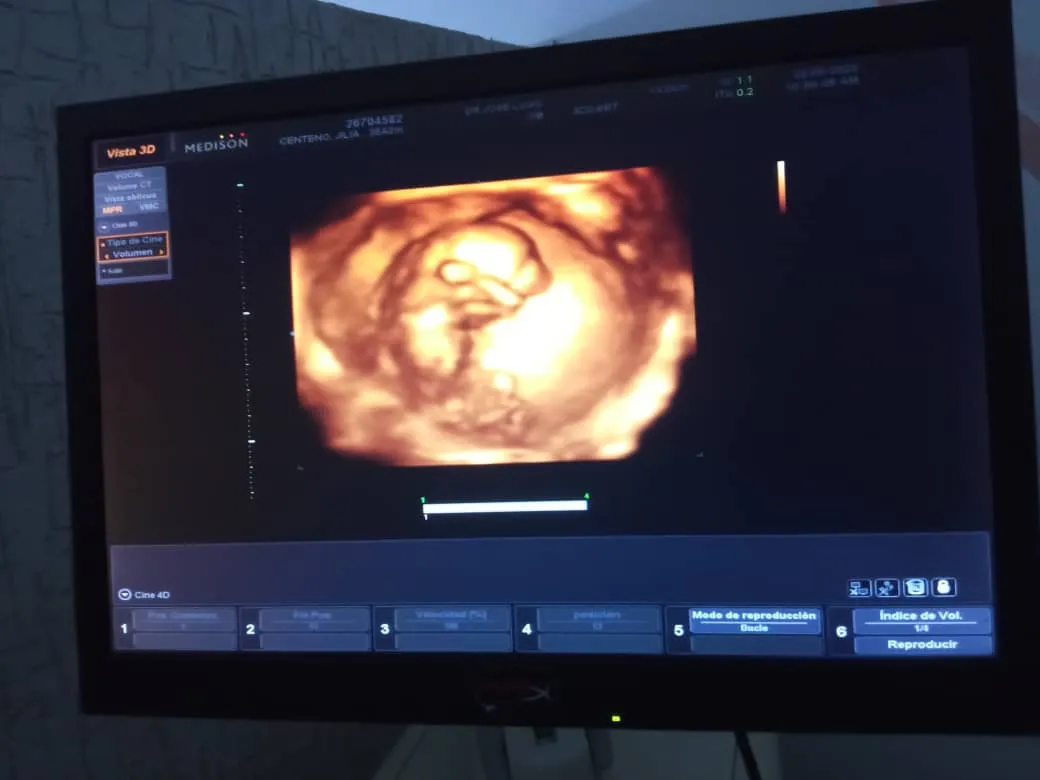

Salimos el día de ayer a celebrar la noticia que mi nieta Gillians va a tener un bebé, luego de tener una relación de cinco años, este sería mi primer bisnieto y sentimos que era un motivo importante para celebrar, así que nos fuimos al centro comercial a disfrutar de un delicioso almuerzo.

We went out yesterday to celebrate the news that my granddaughter Gillians is going to have a baby, after a five year relationship, this would be my first great grandchild and we felt it was an important reason to celebrate, so we went to the mall to enjoy a delicious lunch.